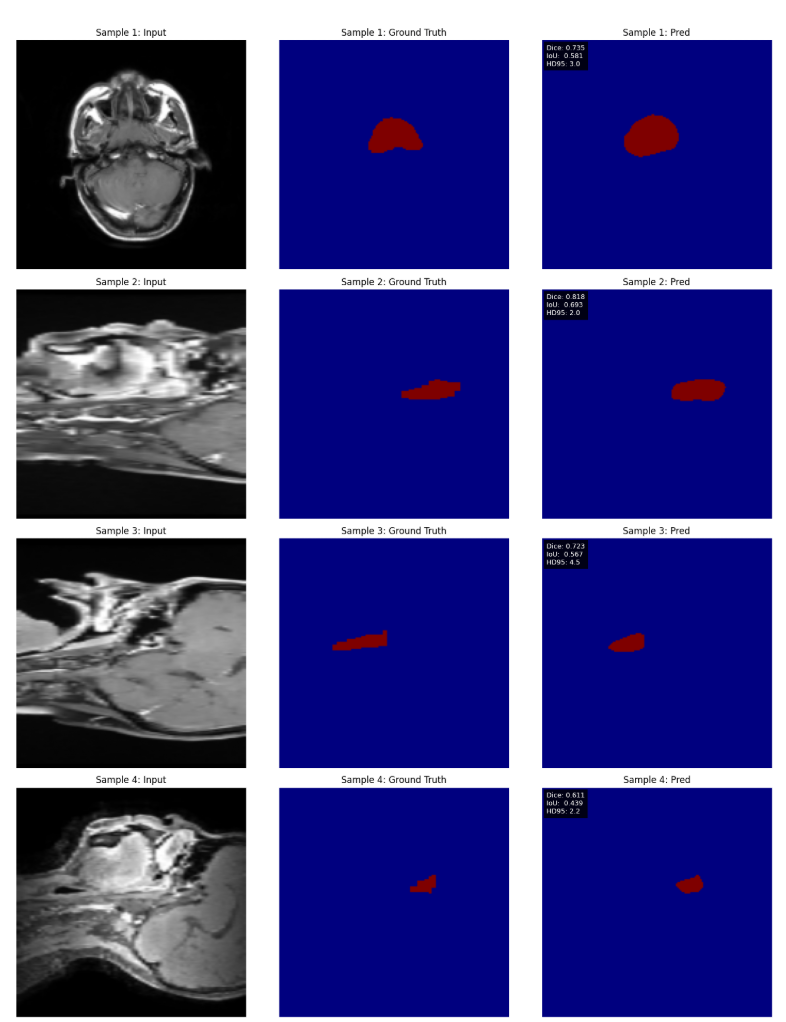

实验结果

给出的结果是BraTS在12.5%掩码率时候效果最好,但是只测试了单个数据集,实际上本文最后使用的还是原MAE的75%mask。

BTCV:前两行 BraTS:后两行

在没有MAE预训练的情况下,坏死的核心节段几乎不存在。

与不具有预训练权重的相应模型相比,应用预训练权重时的分割结果存在显著差异。